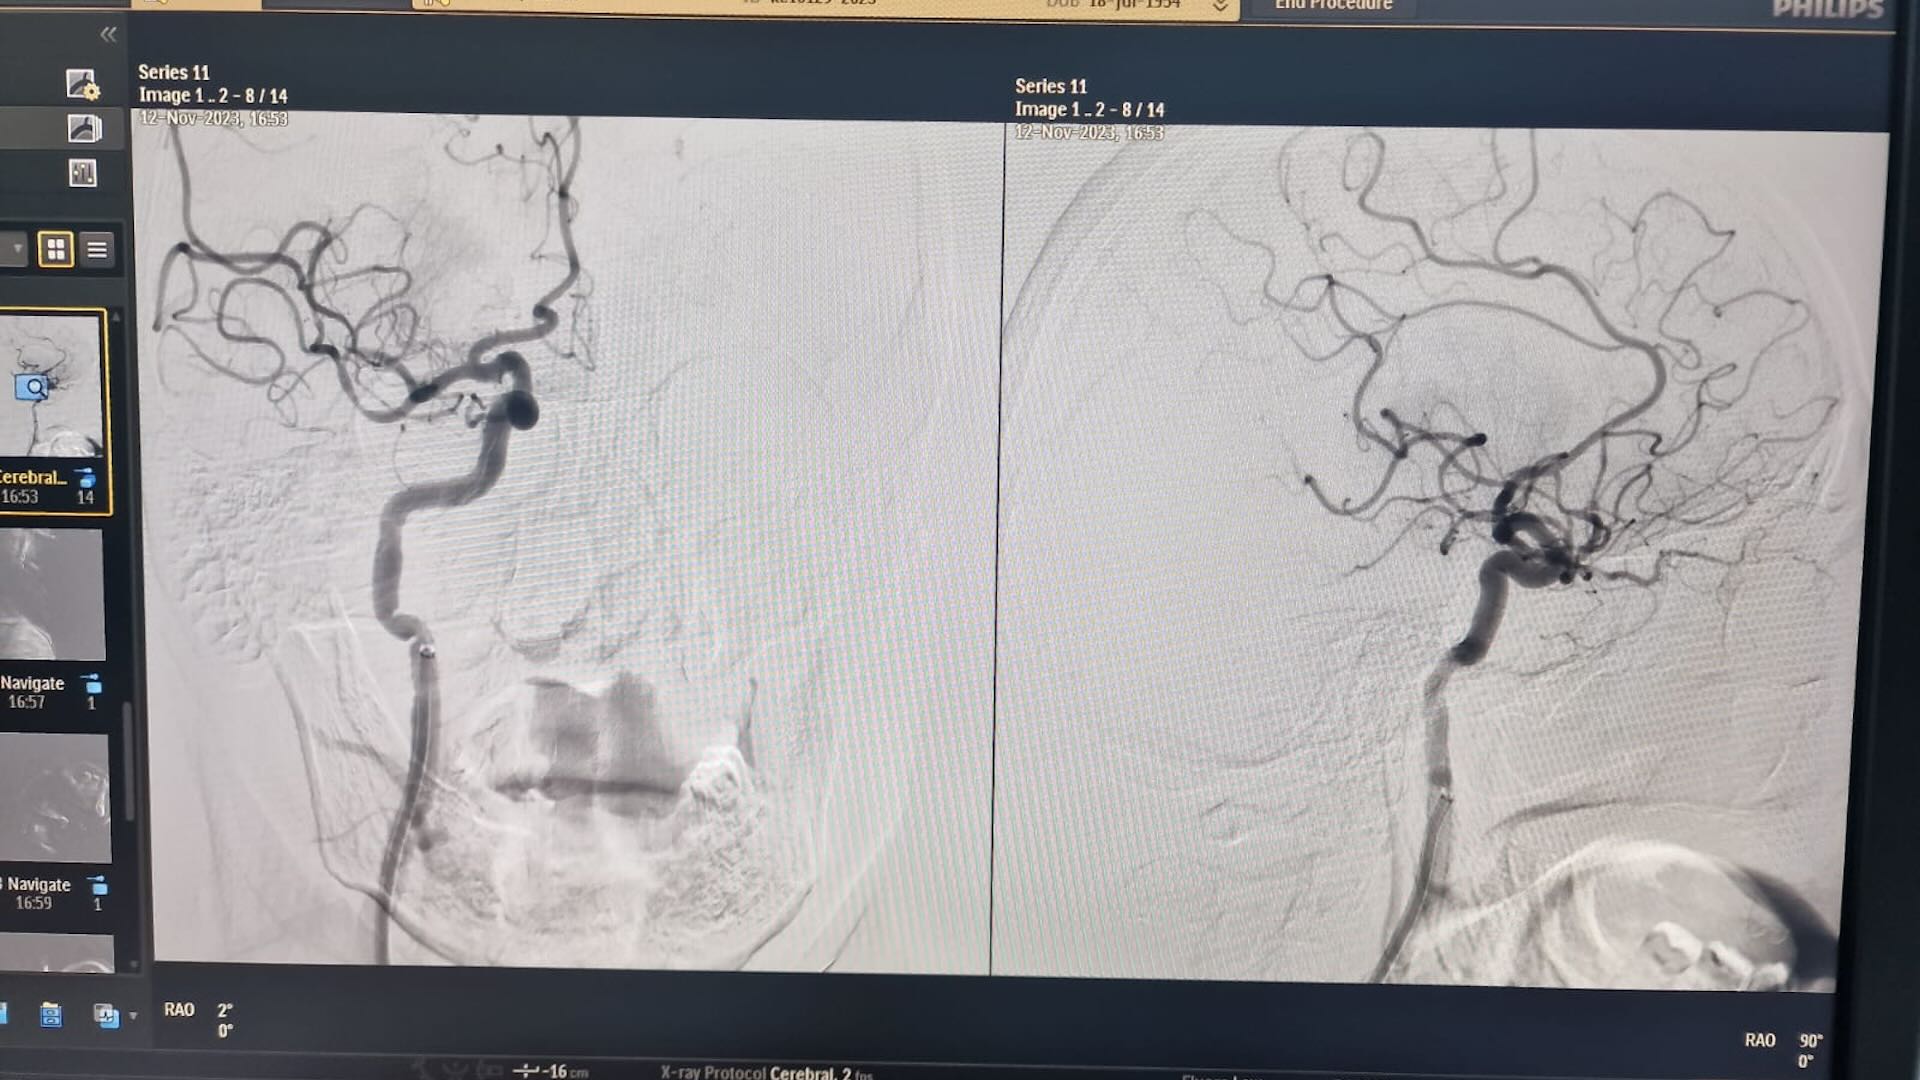

«Мы провели операцию, включающая селективную церебральную ангиографию и тромбоэкстракцию из средней мозговой артерии. Операция проходила под местной анестезией и прошла успешно»,- делится Ермек Сулейменов.

Благодаря мастерству и профессионализму нейрохирургов, тромб был успешно извлечен, а кровеносное русло в бассейне средней мозговой артерии восстановлено. Удивительным образом, на операционном столе наблюдался регресс симптоматики, и черепно-мозговые нервы вернулись к норме.